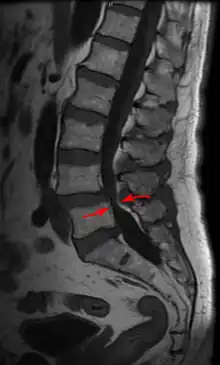

Lumbar vertebra showing central stenosis and lateral recess stenosis.

MRI of a lumbar spinal stenosis L4-L5. L4-L5 antherolisthesis of grade I. Hypertrophy of interspinous ligaments in relation to Baastrup's disease. 67 years old man.